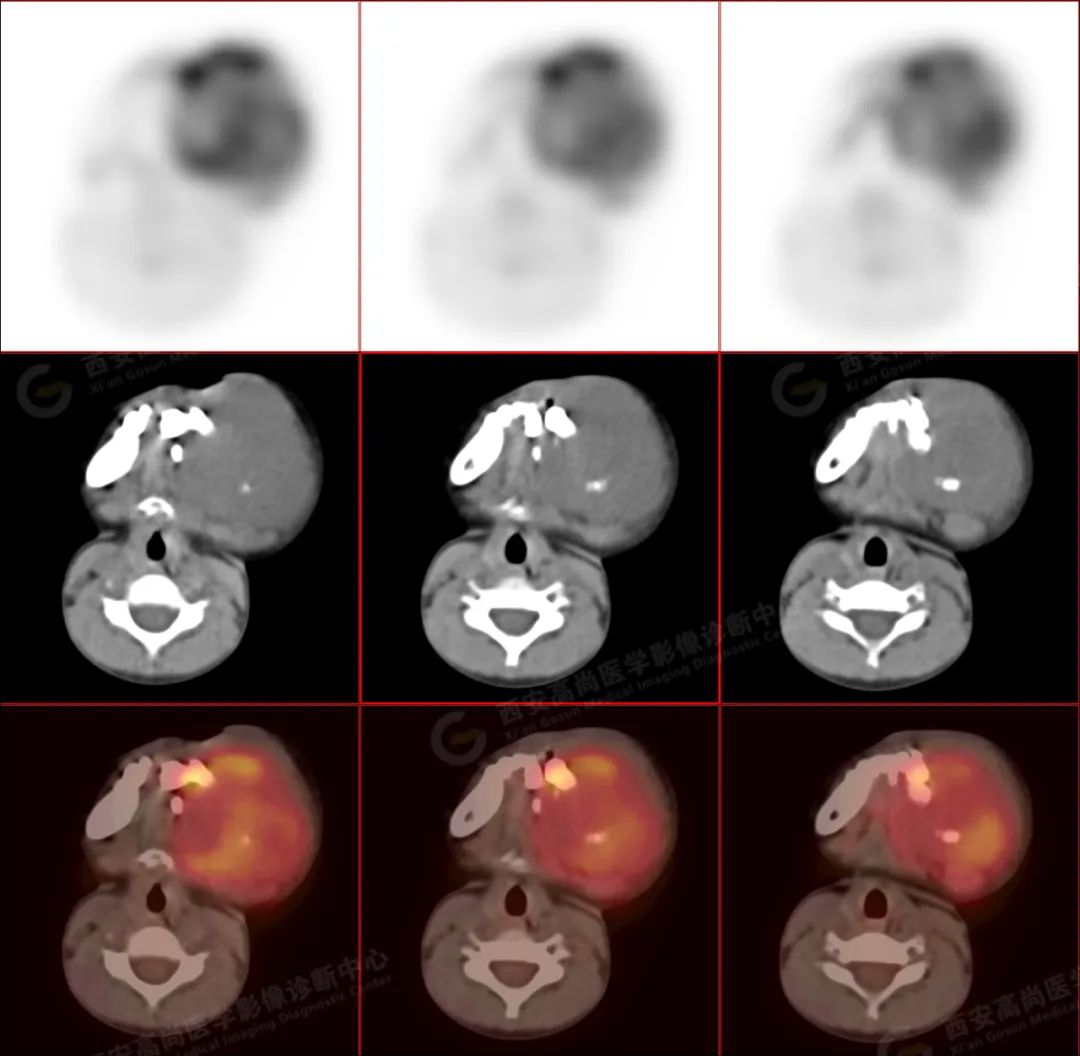

左侧下颌区可见巨大团块状软组织肿块,大小约 6.6 cm×5.8 cm×6.1 cm,向上达左侧颞下窝上缘,向下达下颌前联合,相邻左侧咬肌、颊肌等肌肉组织分界不清楚,左侧口底、咽部、腮腺受压改变,肿瘤包绕及侵犯左侧上颌升支、蝶骨翼突外板,呈 FDG 代谢不均匀异常增高,考虑为恶性病变,横纹肌肉瘤可能性大。

3.PET/CT 能够提供肿瘤代谢信息,并且提供肿瘤分期。分化程度越差的病灶 FDG 代谢明显增高。